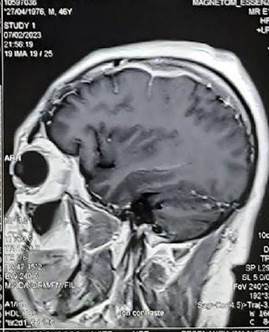

Seis meses antes de la admisión, estando medicado con dexametasona 8 mg/día, presentó cefalea de moderada intensidad que no cedió con analgésicos, siendo hospitalizado nuevamente. En esta admisión se le realizó otra RMN cerebral (figura 4) donde se evidenció un engrosamiento meníngeo frontal izquierdo, tanto en duramadre como de la leptomeninge. Con respecto al estudio previo había incremento del grosor y de la captación de la leptomeninge y presencia de leve edema cerebral. Se administró dexametasona 32 mg/día por 7 días, disminuyendo progresivamente la dosis hasta 12 mg/día. Tuvo mejoría inicial de la cefalea, pero luego se tornó persistente. Luego de estar hospitalizado 3 meses se realizó otra biopsia de meninges por craneotomía, siendo el informe patológico: “tejido dural fibroso con hiperplasia meningotelial. Al examen microscópico se encontró la duramadre engrosada, fibrótica, con algunos focos inflamatorios de células linfomononucleares y también algunos vasos pequeños; se reportaron algunos nidos sólidos de células meningoteliales y ocasionales cuerpos de psammoma, con inmunofluorescencia negativa para IgM, IgG, IgA, C3, C1q y fibrinógeno”. Además, se obtuvo PCR (reacción de la polimerasa en cadena) para Mycobacterium tuberculosis negativo y un resultado ANCA positivo en sangre periférica (ver tabla 2, 3 meses antes del ingreso).

Engrosamiento meníngeo frontal izquierdo, tanto en duramadre como de la leptomeninge. Con respecto al estudio previo se ha incrementado el grosor y la captación de la leptomeninge y hay leve edema cerebral en el sector del engrosamiento leptomeníngeo en comparación con estudio previo. Imagen quística en la cisterna supra cerebelosa que aplana el cerebelo.